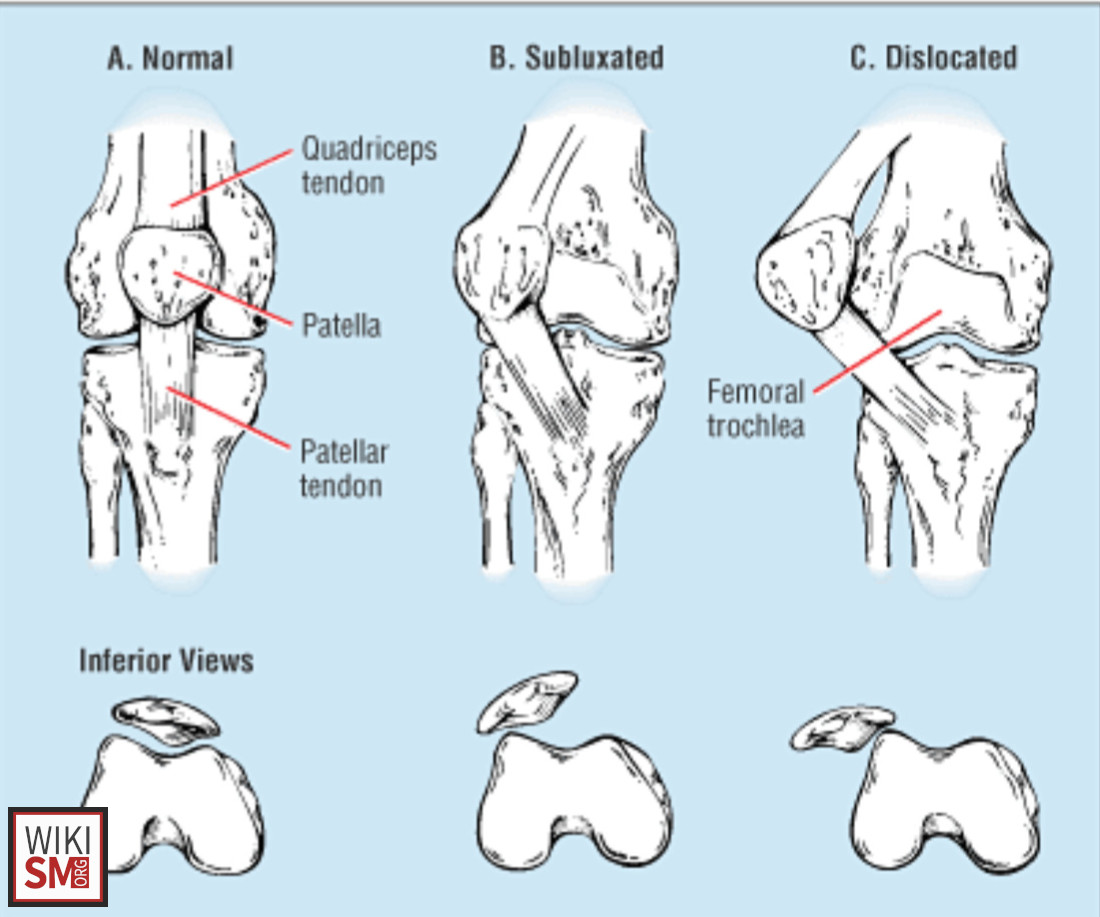

Expand your clinical knowledge with WikiSM.org —a comprehensive resource for sports medicine, MSK exams, and rehabilitation—and MedEdCases.com for real-world, case-based emergency medicine learning